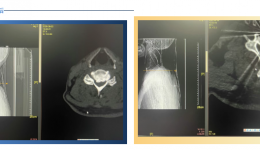

• 看茂医丨UBE微创技术助六旬老人重拾生活希望

看茂医丨UBE微创技术助六旬老人重拾生活希望

“我才六十出头,难道余生都不能正常走路,靠人照顾?”病床上的陈伯紧攥着老伴的手,声音哽咽。六旬老人面临瘫痪茂医团队微创方向精准施治61岁的陈伯(化名)自去年秋天开始,逐渐感到双腿发麻。起初他并未在意,以为只是劳累所致。然而短短几个月...